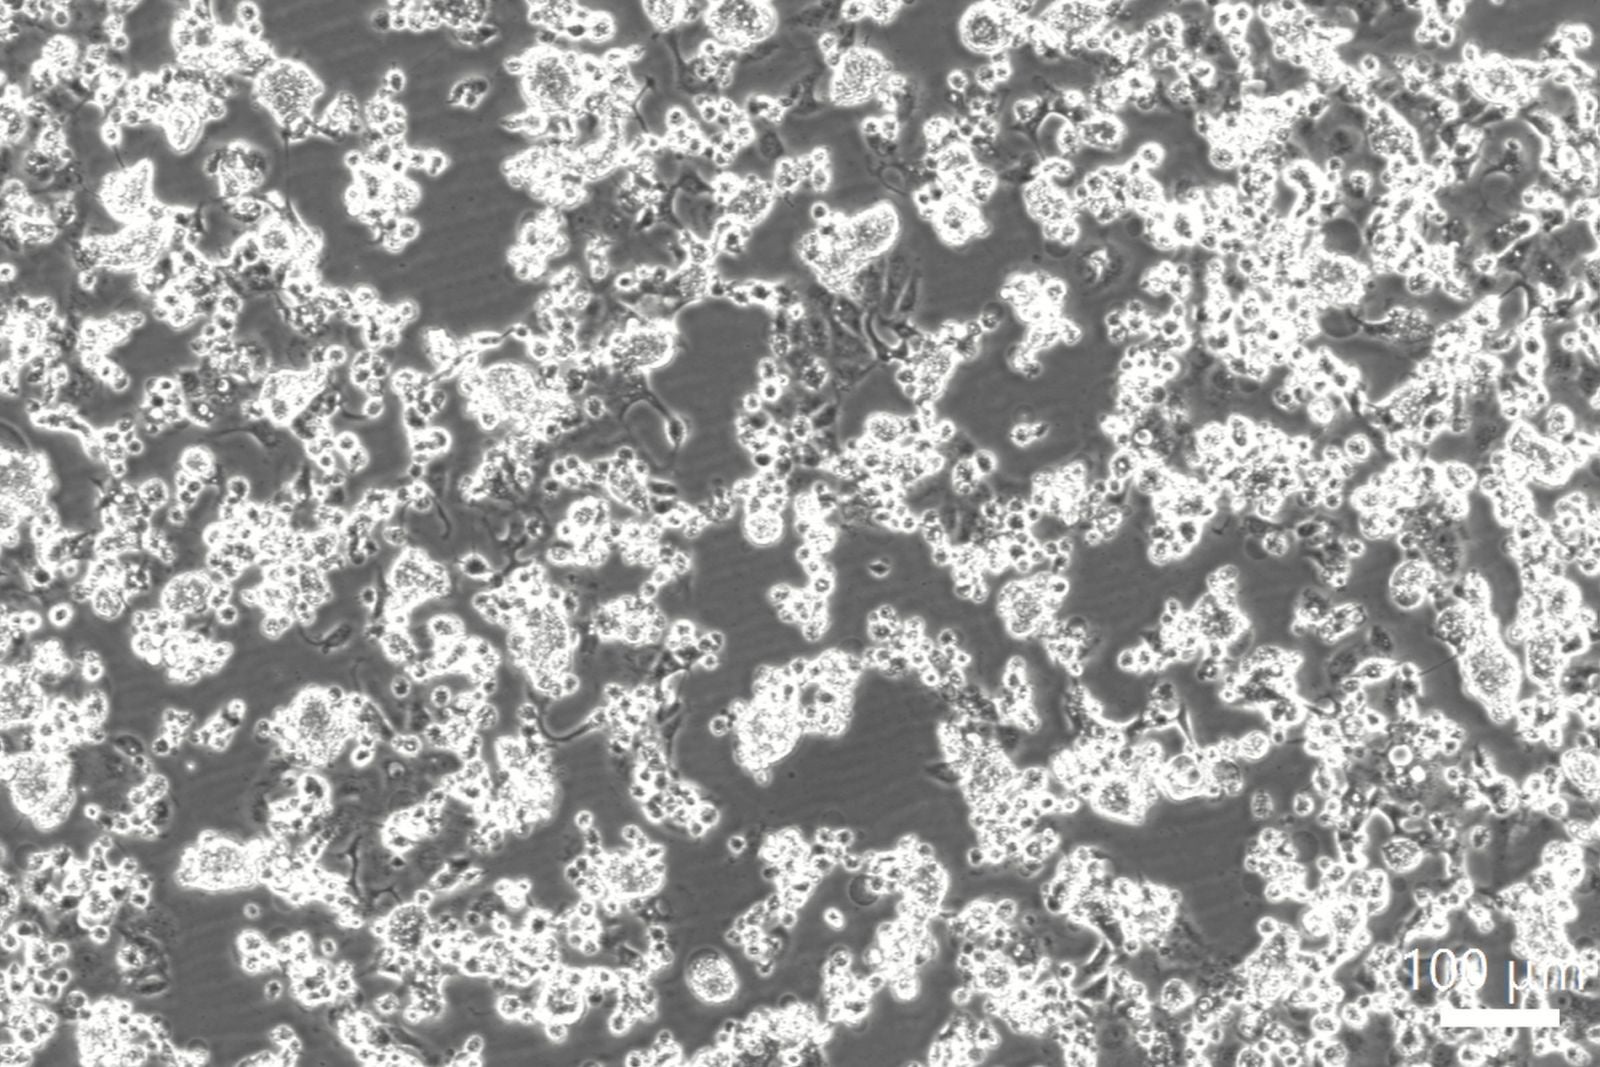

透過型電子顕微鏡写真:ナノイー(帯電微粒子水)照射あり

そこで、ナノイー(帯電微粒子水)による新型コロナウイルスの不活化メカニズムに焦点を当て、ナノイー(帯電微粒子水)の曝露有無によるウイルスの構成成分ごとの影響や、細胞へのウイルスの結合量を測定しました。その結果、ウイルスを構築する脂質二重膜やタンパク質、ゲノムRNAと多段階で作用する様子が確認されました。さらに、ナノイー(帯電微粒子水)を曝露したウイルスは細胞への結合能力が失われることで感染が抑制されることが示唆され、ナノイー(帯電微粒子水)による新型コロナウイルスの不活化メカニズムの一部が明らかになりました。なお、今回の検証は密閉された試験空間での結果であり、実使用空間における効果を検証したものではありません。